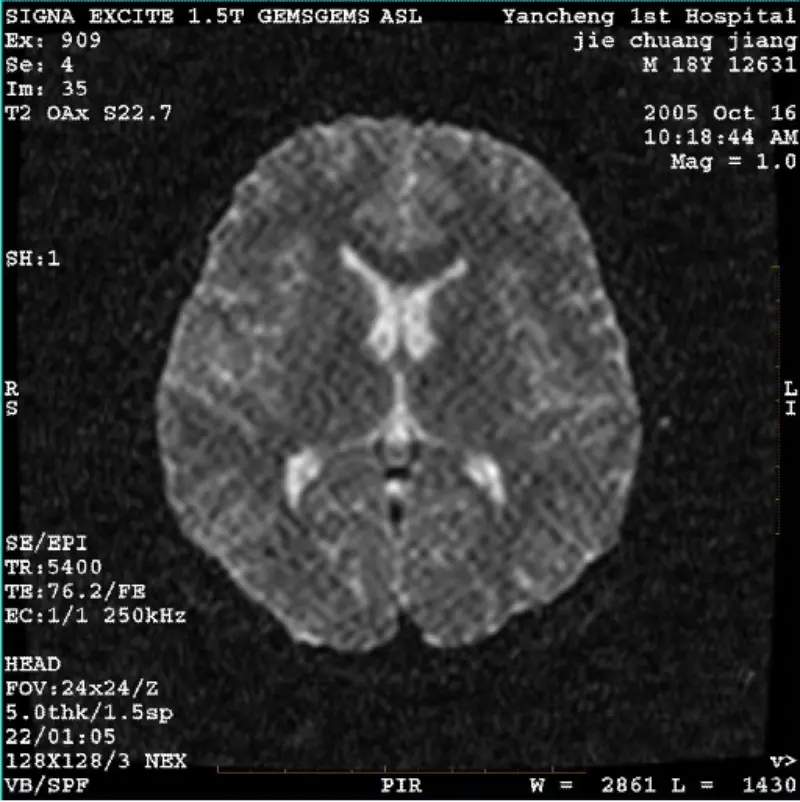

続きを読むシステム:MR 0.35T オベーション 病院: 大慶油田総合病院 問題/症状 FRFSE および GRE プロトコルの画像にはゴーストがあり、SNR が低い場合があります。 システム: MR 0.35T Ovation 病院: 大慶油田総合病院 問題/症状 FRFSE および GRE プロトコルの画像にはゴーストがあり、場合によっては SNR が低い画像が表示されます あるシリーズに登場します。ただし、SE プロトコルのイメージは正常です。 画像を添付してご覧ください。画像 あるシリーズに登場します。ただし、SE プロトコルのイメージは正常です。 画像を添......